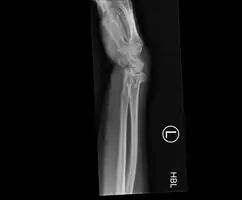

![]() | |

| An X-ray showing a Colles' fracture | |